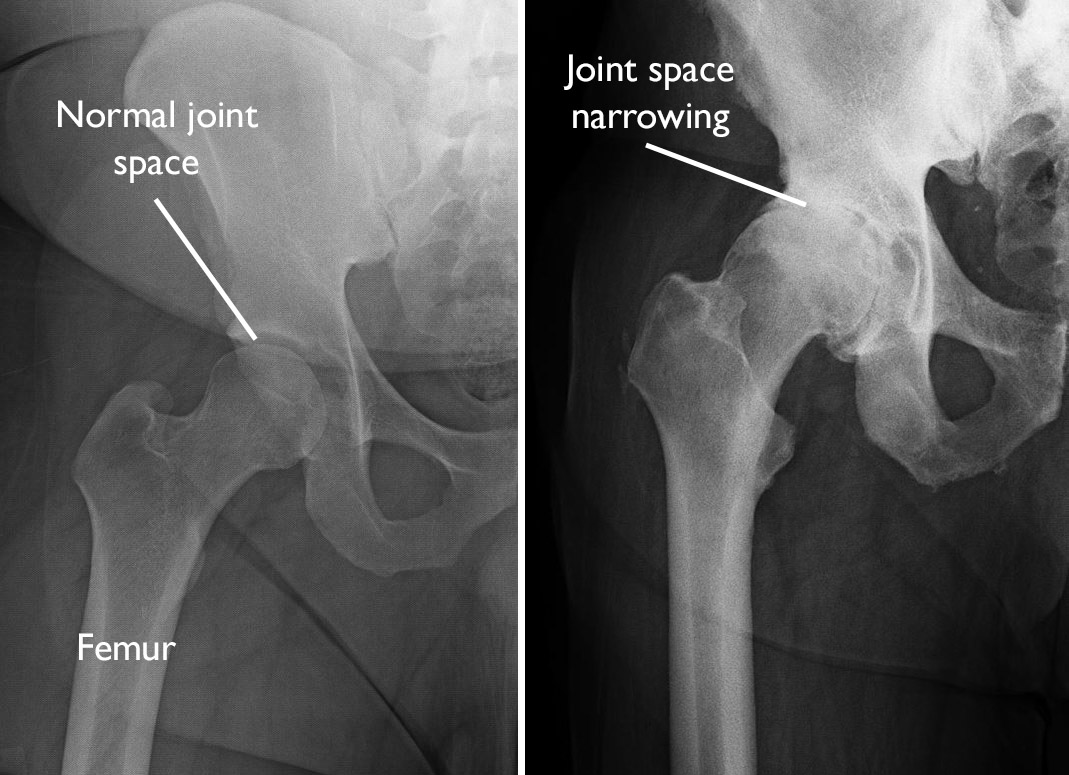

Hip Osteoarthritis X Ray Classification . The original paper 1 graded oa at the. The hip osteoarthritis mri scoring system (hoams) scores with respect to 14 articular. Osteoarthritis of the hip can be classified into primary and secondary, depending on whether or not it is due to a known predisposing factor. Scoring systems exist for mri classification of hip osteoarthritis. Osteoarthritis of the hip can be graded according to its severity. Hip osteoarthritis is degenerative disease of the hip joint that causes progressive loss of articular cartilage of the femoral head and acetabulum. The most commonly used radiographic classification system for osteoarthritis of the hip joint is the kellgren. The kellgren and lawrence system is a common method of classifying the severity of osteoarthritis (oa) using five grades.